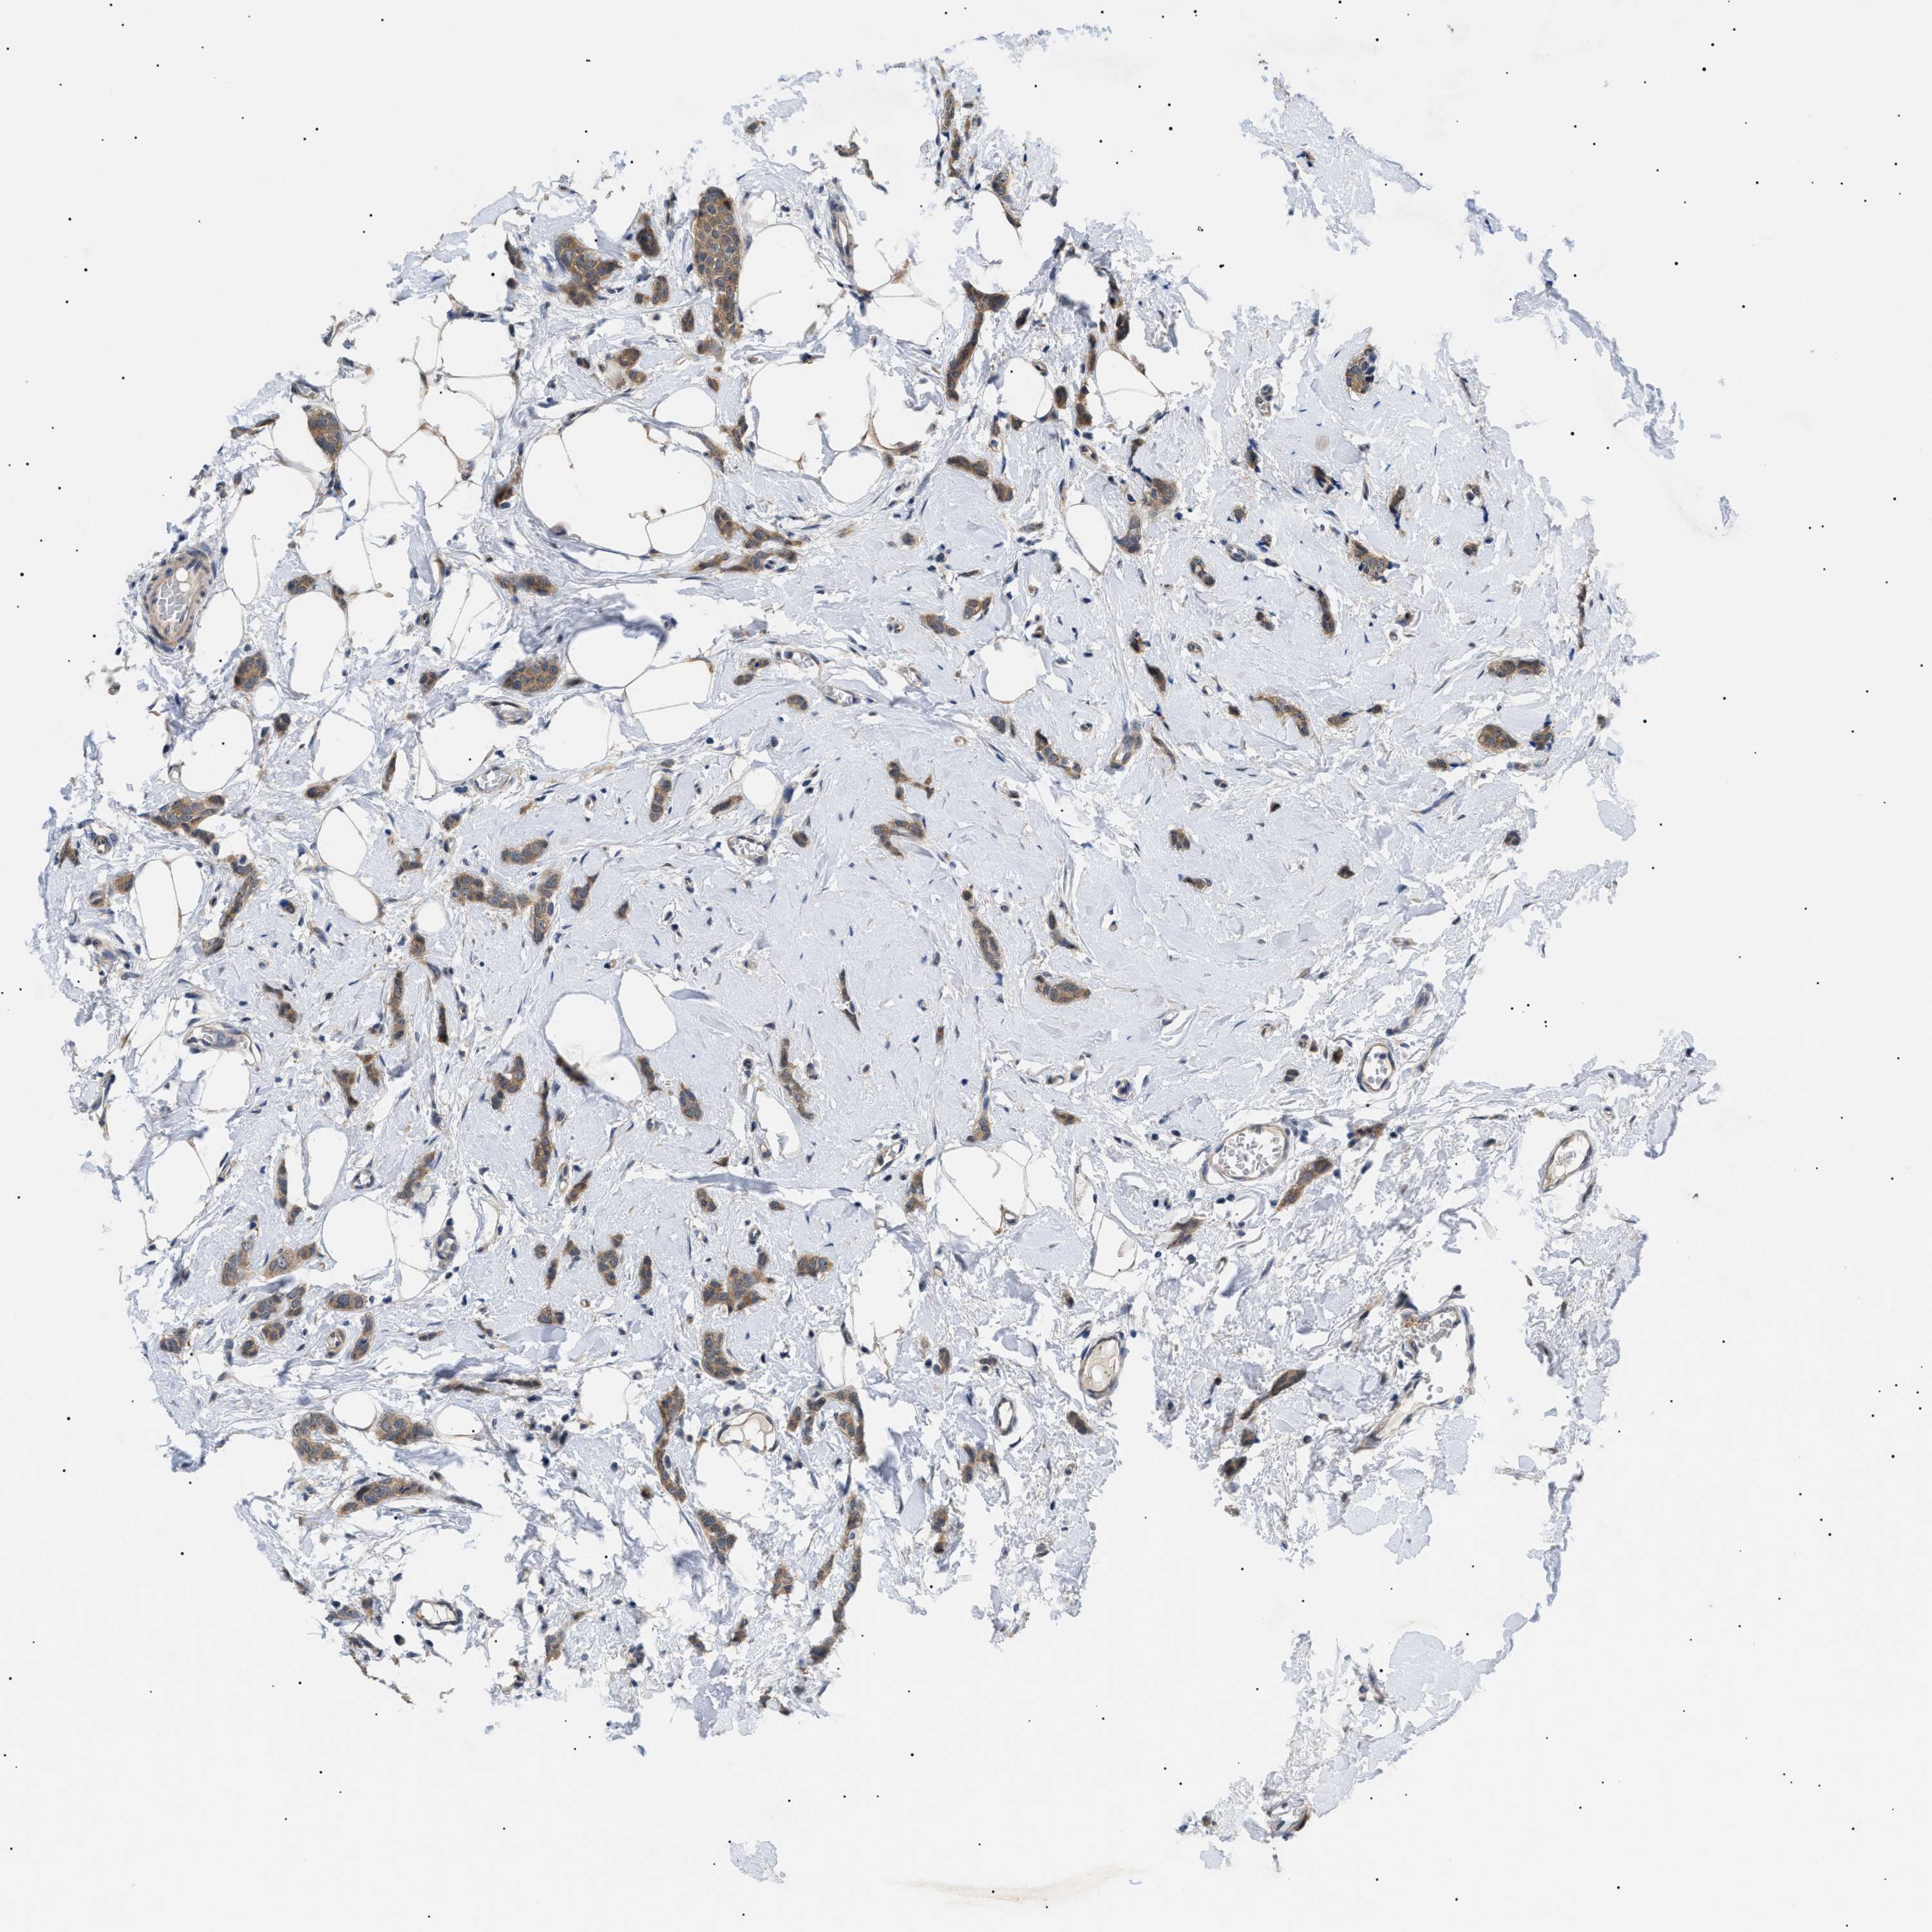

BRCA TCGA BRCA VALIDATION PROTEIN EXPRESSION